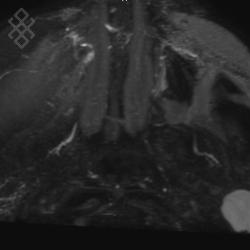

IRM des Glandes salivaires (Sialo-IRM)

L'examen dure en moyenne 35 min. Vous entendrez un bruit caractéristique à l'IRM et qui peut faire penser à un marteau piqueur. Durant les séquences il faudra essayer de ne pas avaler la salive pour limiter les mouvements de déglutition. Le manipulateur en radiologie vous injectera le produit de contraste en cours d'examen.